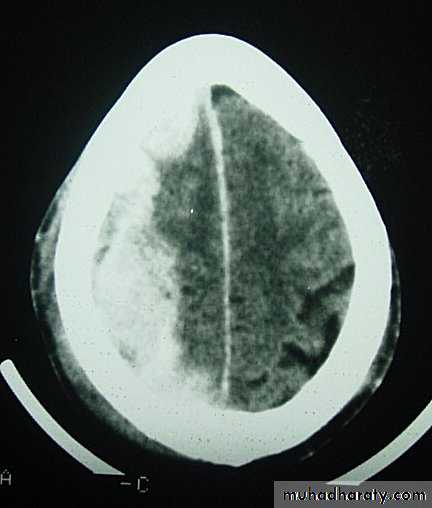

Acute Subdural Haematoma

Clinical Picture: patient will present with a picture similar to that of an extradural haematoma, but there is persistent loss of consciousness with no lucid interval.

Ct scan will show a concave hyperdence collection because blood follows the subdural space over the convexity of the brain.

Acute Subdural Haematoma are rapidly evolving lesions and early evacuation via craniotomy is mandatory.